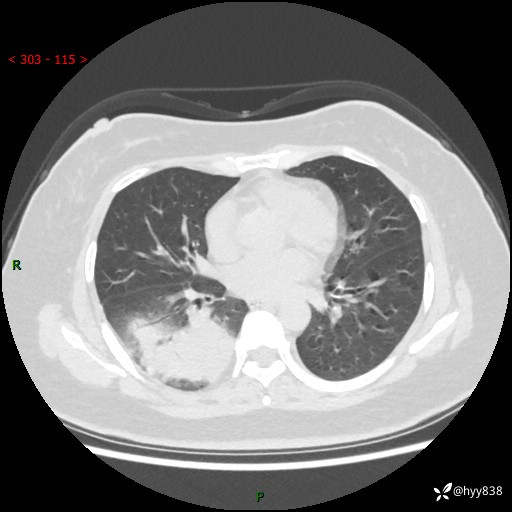

大叶性肺炎的表现形式,晒晒鉴别诊断吧…结果公布~

简要病史:患者8天前无明显诱因出现咳嗽、咳痰,为绿色脓痰,无明显加重与缓解因素,无高热、寒战,无呼吸困难,无大量脓痰,无哮鸣音,于当地医院行胸片示右下肺团块影,性质待定,予口服药物治疗症状未见明显改善,具体药名不详,为求进一步诊治来我院就诊,门诊以“肺占位性病变”收入我科进一步诊治。 患者自发病以来,精神、饮食尚可,睡眠欠佳,大小便正常,体力、体重未见明显异常。

辅助检查:CT

胸部CT平扫

增强动脉期+静脉期